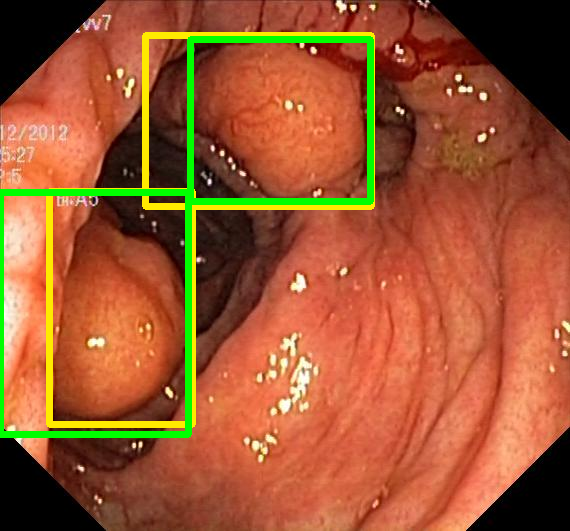

We evaluate the resulting object detection models using the test data, which is pre-processed in the same manner as the validation data, with AP@[.5:.95] (AP for conciseness), AP@.5 (AP50), and AP@.75 (AP75) computed for predicted bounded boxes with a confidence score \geq0.05. For all metrics, a higher value indicates better performance. The results are presented in Table VI, and some examples for predicted bounding boxes with a confidence score \geq0.5 are shown in Fig. 1.

Figure 1: Targets (yellow bounding boxes) and predictions (green bounding boxes) for two randomly selected instances of the Kvasir-SEG test set. For conciseness, we denote ResNet50s with RN, ViT-Bs with VT, Hyperkvasir-unlabelled with HK, ImageNet-1k with IN, MoCo v3 with MC, Barlow Twins with BT, MAE with MA, supervised pretraining with SL, and no pretraining with NA-NA.